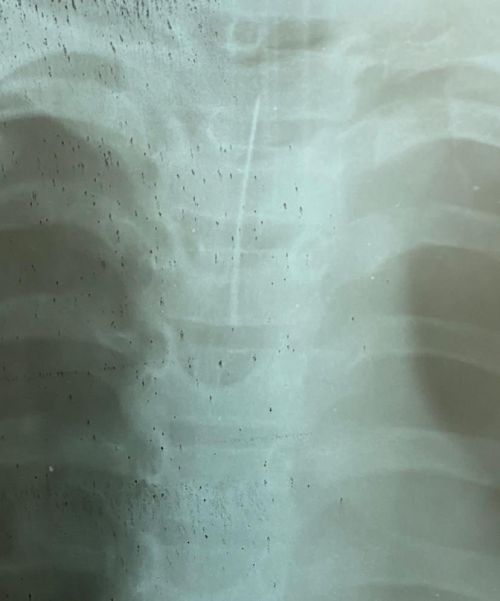

1 декабря на странице Черкасской областной детской больницы в Facebook появилась информация, что в медучреждение доставили ребенка с иголкой в горле.

Извлекали опасный предмет врачи из трех отделений: приемного, хирургического и анестезиологического. Благодаря слаженной работе команды специалистов все прошло успешно, здоровью и жизни ребенка ничего не угрожает.